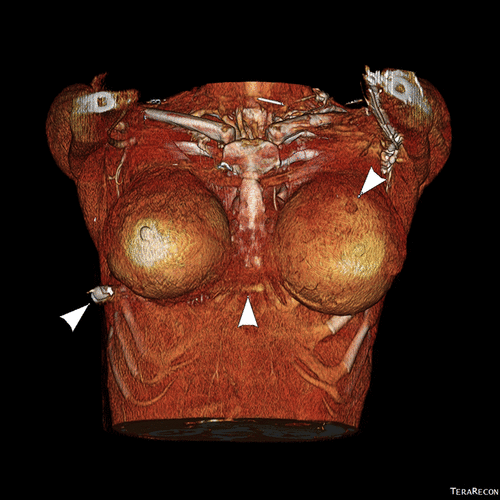

и изображений с 3D модулированием (фото 10 и 11) в сочетании с клинической оценкой поверхностных ран.

Figure 10. Трехмерное (3D) объемное изображение груди.

Figure 11. Трехмерное (3D) объемное изображение. Изображение демонстрирует входное отверстие в левой части грудной клетки (стрелка справа), путь пули с разрывом мягких тканей грудины (средняя стрелка) и пулю в правой боковой стенке грудной клетки (стрелка слева).

Реконструированные проекционные изображения демонстрируют выход пули из левого имплантата в заднюю часть правого имплантата. Также обнаружена пуля в правой грудной стенке. На основании клинической траектории входа пули и рентгенологической оценки единственным источником отклонения пули является левый грудной имплантат.